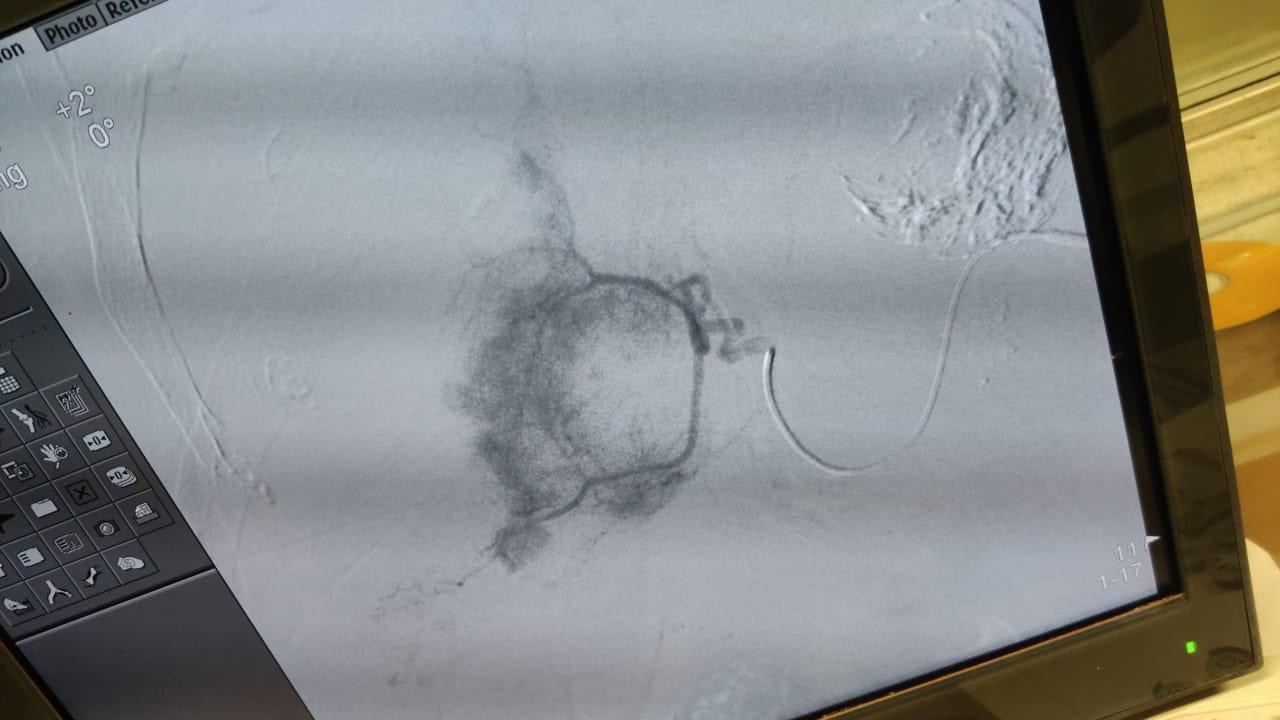

وقال بيان صادر عن كلية الطب بجامعة كفر الشيخ، إن الفريق الطبي تمكن من حقن الشريان المغذي لورم الكبد selective embolization والتحكم في نزيف شديد بعد فشل الطرق التقليدية من نقل دم للمريض وكذلك العلاج بمثبطات التجلط.

وتابعت كلية الطب بجامعة كفر الشيخ، أن الفريق الطبي من قسم الاشعة التداخلية هو من أجرى هذه الجراحة ومكون من الدكتور محمود غلاب، والدكتور عمرو أمين، والدكتور محمد الصيرفي، حيث قدمت لهم الكلية الشكر على إجراء هذه الجراحة.